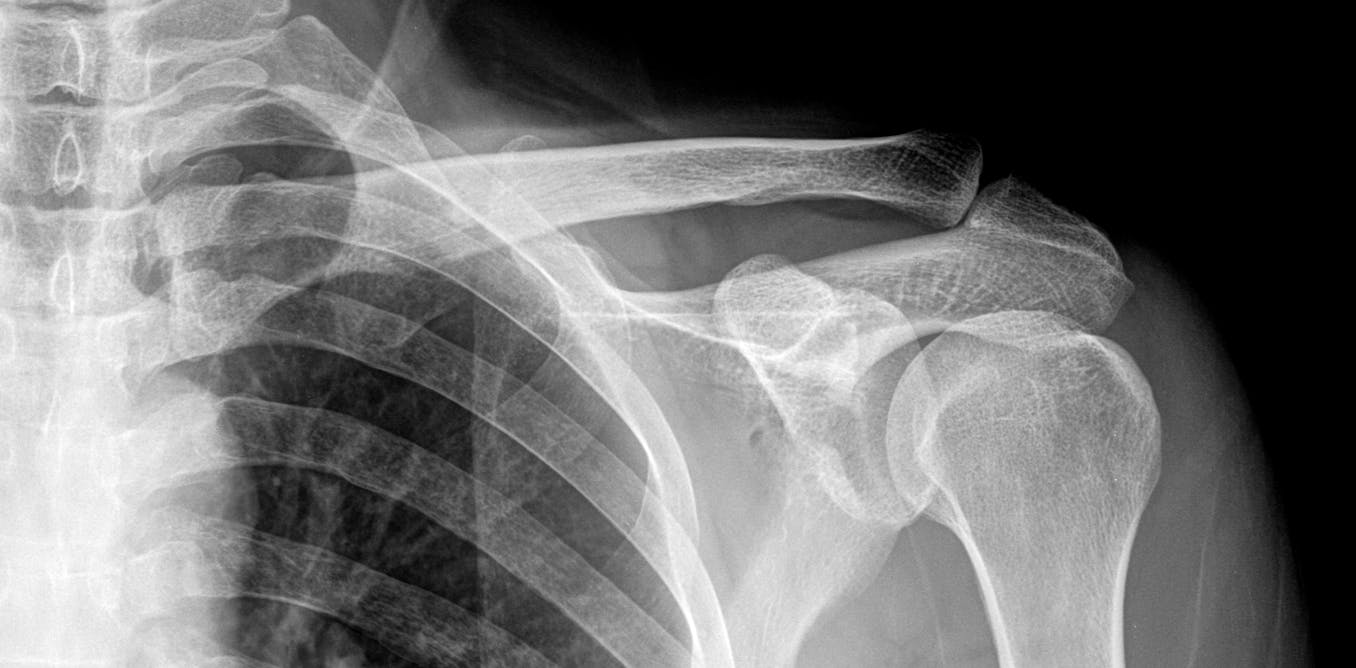

Рентген снимок плечевого сустава в норме.

Артроз плечевого сустава рентген.

Артроз акромиально-ключичного сочленения рентген.